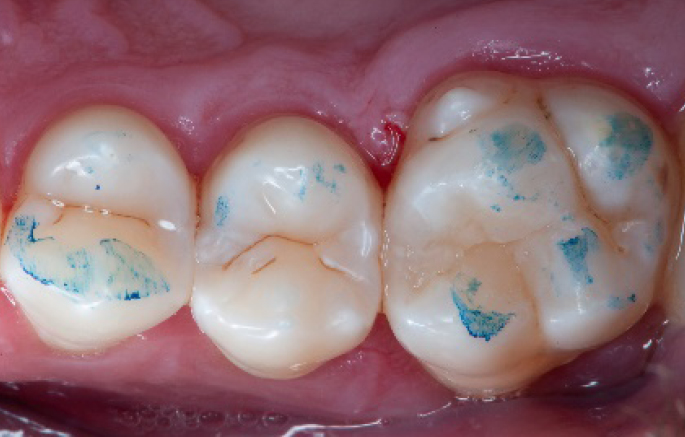

Step 13:

Occlusal check